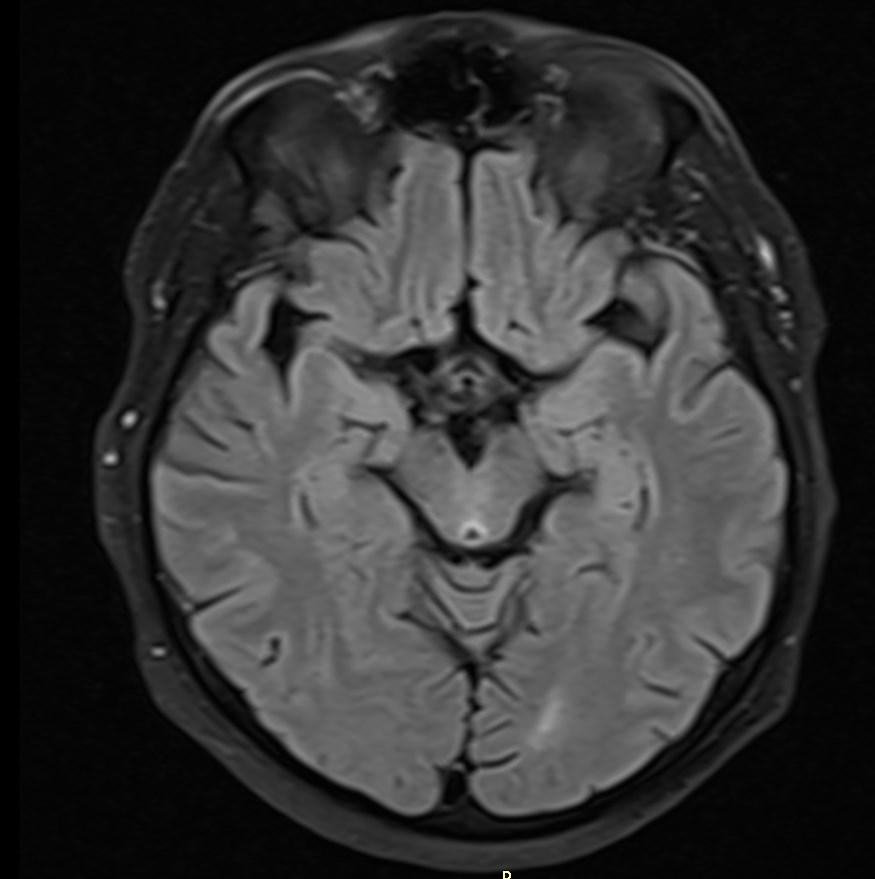

MRI images revealed hyperintensities in the periaqueductal region and the medial thalami.

T2/FLAIR: symmetrically increased signal intensity in the mamillary bodies, dorsomedial thalami, tectal plate, periaqueductal area, and around the third ventricle.